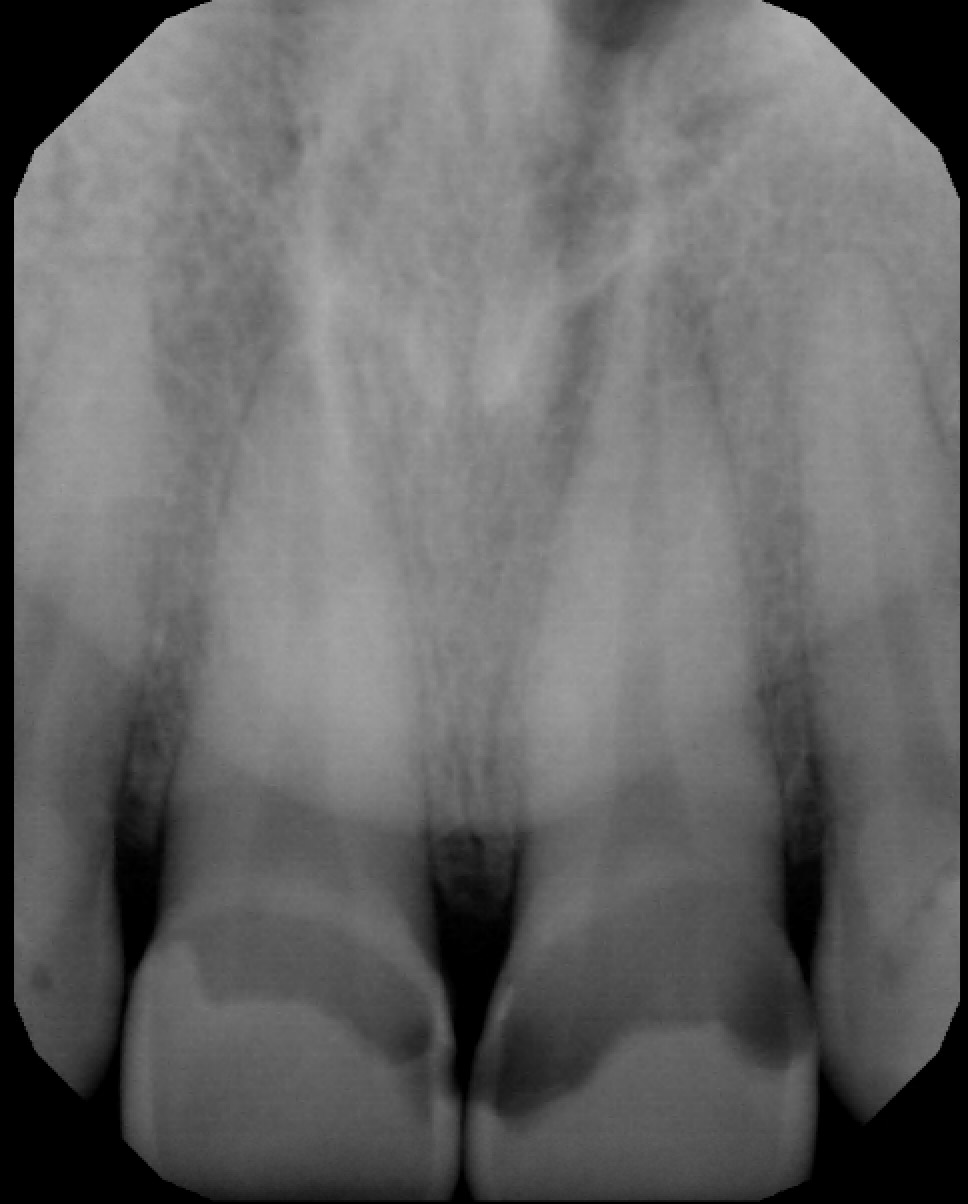

• Conclusion: The radiolucencies seen at the apex of 11 and 21 (US # 8 and 9) were not periapical lesions. I retook a PA with a different angle (see next slide)

• Prostho consultation: It was decided to restore 21 the same way 11 was restored due to the high quality outcome of the restoration and reevaluate the need for RCT, CCL and crown in 4 weeks, hoping the pulp will reverse to normal and not be sensitive anymore.

• Additional radiographs

Note: No periapical lesion is noted on 11 and 21 (US # 8 and 9).